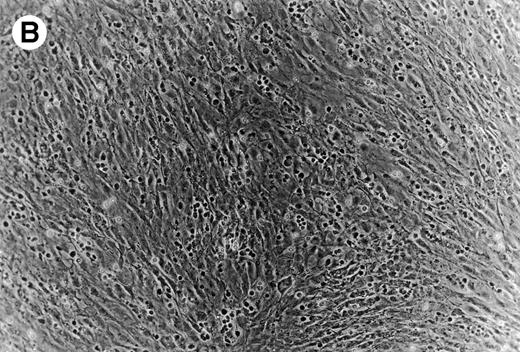

(A) Representative phase contrast photomicrograph of pseudoemperipolesis of CLL B cells after 2-hour culture on the heterologous murine stromal cell line, M2-10B4. Cells that had not migrated beneath the stromal cells washed off, and the stromal cell layer containing the migrated CLL cells was photographed (200x magnification). Pseudoemperipolesis is characterized by the dark appearance of lymphocytes that have migrated into the same focal plane as the stromal cells. (B) For comparison, this photomicrograph shows reduced pseudoemperipolesis after pretreatment of CLL cells with pertussis toxin.

Role of SDF-1 in pseudoemperipolesis of CLL B cells.

To establish the role of SDF-1 in the migration of CLL cells into the stromal layer, we used inhibitors that specifically or nonspecifically interfered with the interaction of SDF-1 or CXCR4 on CLL cells. Pertussis toxin was the strongest inhibitor of CLL cell pseudoemperipolesis: only 14% ± 11% (mean ± SD; n = 6) cells compared with untreated control samples (100%) had migrated after 2 hours. Significant inhibition was also observed after SDF-1α pretreatment and addition to the coculture (35% ± 19%; n = 6), and anti-CXCR4 MoAb preincubation of CLL cells (58% ± 16%; n = 6; Fig 8B).